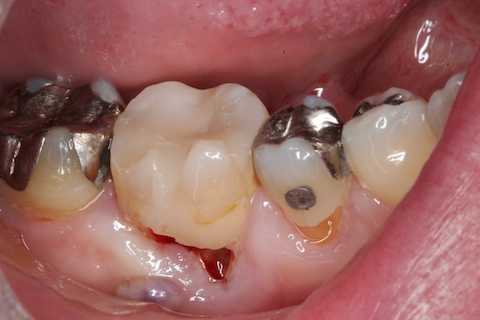

残根上のCR8 2025.10.28